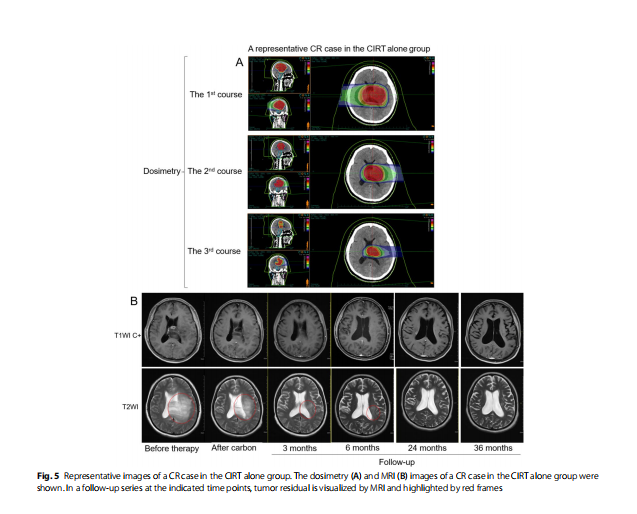

Subgroup analysis by gender, grade, IDH1/2 mutation status, and KPS scores

To explore the clinical characteristics that might influence survival in patients who received CIRT alone or Photon+ CIRTboost, we performed subgroup PFS and OS analysis. For CIRT alone therapy, female patients and patients with IDH1/2 mutations had significantly better PFS (Fig. 3A and C) and OS (Fig. 4A and C) compared to their respective counterparts. No significant difference was observed by WHO tumor grade or KPS score separation (Figs. 3B and D and 4B and D). For Photon+ CIRTboost therapy, no significant difference in PFS or OS was observed in all subgroup analyses (Figs. 3E-H and 4E-H). The typical dosimetry and MRI images of two representative CR cases in CIRT alone (Fig. 5A-B) and Photon+ CIRTboost (Fig. 6A, B) were provided. For CIRT alone, three layered doses were designed, including GTV: 60.0 Gy (RBE)/20 Fx, V1: 30.0 Gy (RBE)/10 Fx, V2: 45.0 Gy (RBE)/15 Fx. Sequential boosting was performed using a three-course plan, gradually decreasing the target area (Fig. 5A).